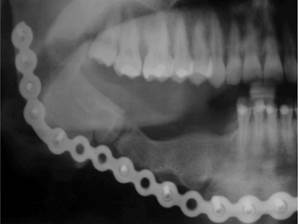

There was no neurological involvement (mandibular nerve). The X-ray examination showed a mixed density multilocular osteolytic lesion, expanding towards cortical and producing first molar and second premolar root resorption (Figure 1).

Complete resection of the lesion was performed with safety margins from the right canine to the ipsilateral mandibular ramus, inserting a reconstruction plate and reconstructing soft parts. Two months after the initial procedure and with clean margins, mandibular reconstruction was carried out with iliac crest-free grafting. During a follow-up 1 year and a half afterwards, resorption of the graft with mandibular continuity was observed. However, one year later, due to the patient’s personal reasons, the mandibular defect was corrected by reconstruction with iliac crest-free graft. The osteosynthesis material was removed one year later once the jaw contour continuity had been confirmed (Figure 2).